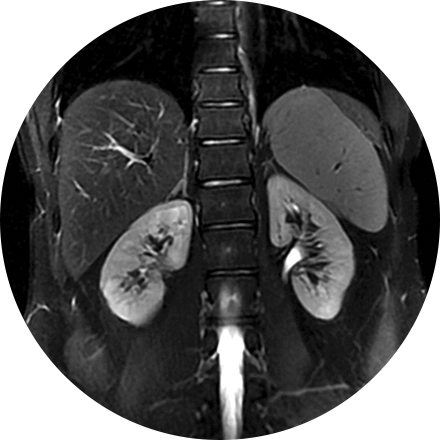

Renal Ultrasound

A renal ultrasound is a safe and painless test that uses sound wavesto produce images of the kidneys and bladder. The kidneys are a pair of bean-shaped organs located toward the back of the abdominal cavity, just above the waist. They remove waste products from the blood and produce urine.